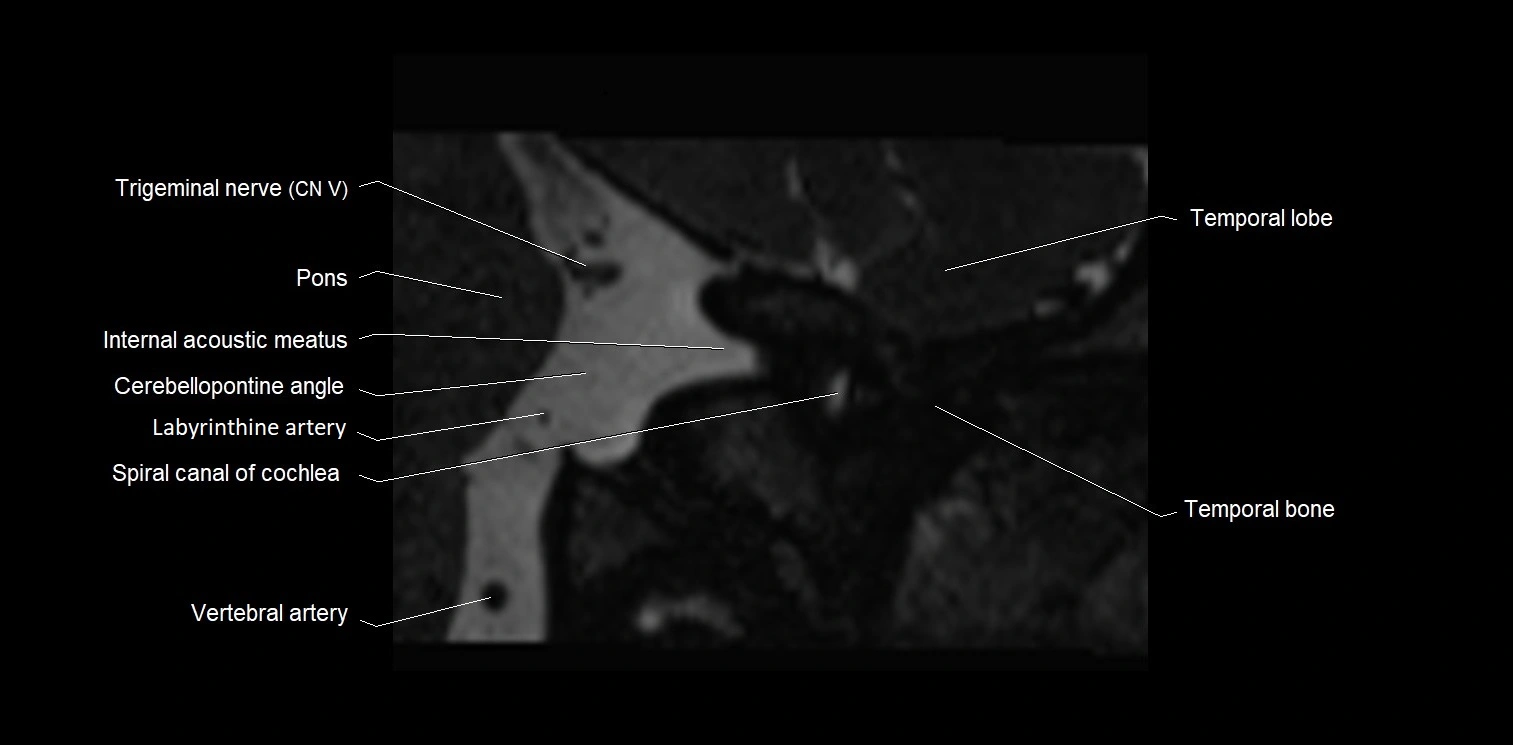

MRI images

image